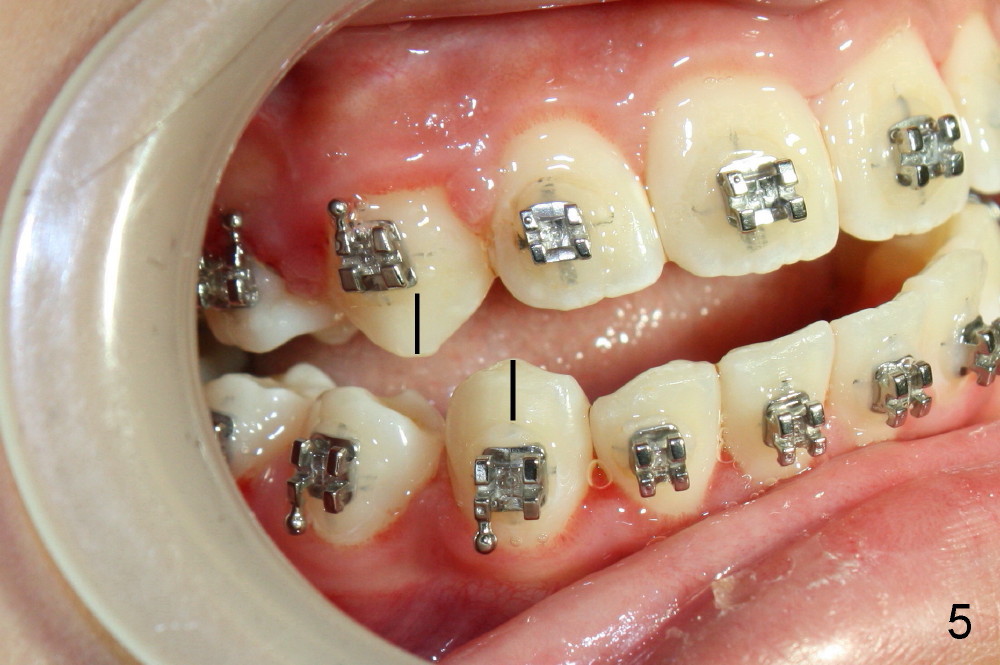

Again due to lack of close monitoring (summer vacation in China), overcorrection occurs (Fig.4-6): from Class II malocclusion to Class III (especially left side (Fig.6 black lines) with anterior open bite and midline shifting (Fig.4 white lines).